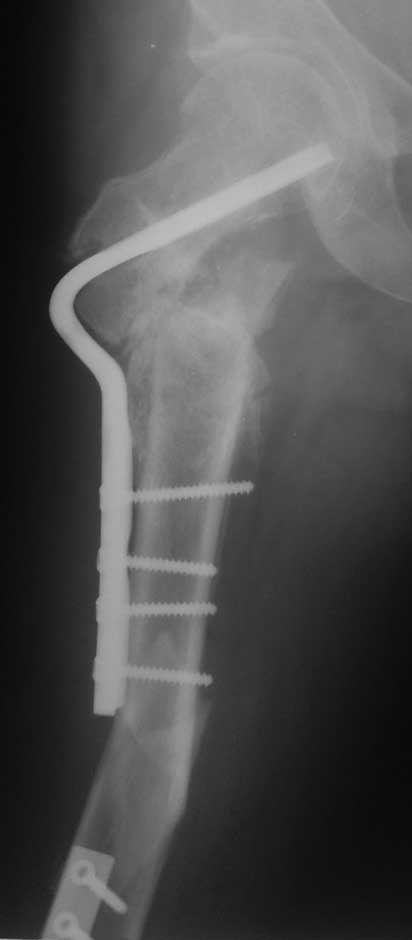

Уважаемые коллеги, помогите пожалуйста с тактикой лечения. Больная 43 лет, подвернув правую ногу, получила простой (А2) перелом правого бедра в с\3, м\у установленными ранее пластинами. В течении 4 недель лечится методом скелетного вытяжения.В анамнезе: в июне 2011г. получила перелом наружного мыщелка правого бедра на фоне консолидированного в порочном варусном положении перелома вертельной зоны (со слов травма 5 лет назад - лечилась консервативно), сопровождающимся укорочением 5 см. В одну операционную сессию выполнен остеосинтез перелома мыщелка бедра Т-образной пластиной и с целью коррекции укорочения выполнена вальгизирующая межвертельная остеотомия с фиксацией клинковой пластиной.На наш взгляд, наиболее простым является накостный остеосинтез диафизарного перелома по передней поверхности бедра, но смущает необходимость образования в последующем дополнительного кожного рубца. Пожалуйста, может быть у Вас есть другие мнения. Зарание благодарен. С уважением А.Гринь. ОКБ №2 г.Тюмень.

На снимке положение клинка идеальное, но шейка в ротации. Из-за неправильного расчета остеотомии не удалось латерализовать диафиз, и конечность находится в чрезмерном вальгусе. При укорочении с вальгусом увеличивает стресс в зоне между пластинами, и конструкция не выдерживает, и при малой травме может осложниться стрессовым переломом.

Для предупреждения чрезмерного вальгуса во время операции сразу ниже клинка снаружи выше линии остеотомии укладывается костный фрагмент, взятый из остеотомии, который переводит диафиз из медиального положения латерально.

При правильной установке клинковая пластина без потери стабильности выдерживает вес пациента. Но здесь получился порочный круг, перелом мыщелка не позволяет нагружать, а без компрессии в зоне остеотомии нельзя добиться сращения. Пластина в данном случае работает как обычный нейтрализатор, хотя должна работать в динамическом режиме. Погоня за двумя зайцами не всегда верный способ, и можно было бы подождать с реконструкцией!

В 120 градусной или в любой реконструкционной клинковой пластине главным является проксимальный, т.е. ближайший к остеотомии винт. Чем ниже остеотомии находится винт, тем больше увеличивается момент рычага, что может привести к несостоятельности (поломке) конструкции. Для вальгусной остеотомии достаточной бывает пластина с двумя отверстиями, но при этом варианте, возможно, длинная пластина пригодится?

Расположение клинка и степень сращения в зоне остеотомии трудно увидеть по одной проекции, и поэтому желательно дополнить исследования КТ и боковыми рентген снимками.

Из возможных операций: я бы предложил провести ретроградную фиксацию бедра после удаления дистальной пластины. При отсутствии полного сращения перелома можно установить пару шурупов спереди и сзади гвоздя, или можно оставить укороченный вариант пластины.

Гвоздь подвести под вертел, и оставить проксимальный винт, а остальные шурупы могут быть через один кортекс. Идеально установить "стоппер", который укоротит клинок и латерализует диафиз. Создаст компрессию!

Из бокового "субвастусного" доступа можно уложить пластину спереди, но тогда надо подождать с нагрузкой. Провокационный антеградный вариант технически сложен, но тогда теряется преимущества сколжения клинка в шейке, и потом клинок не разрушает, как остальные дивайсы, костную структуру в головке.